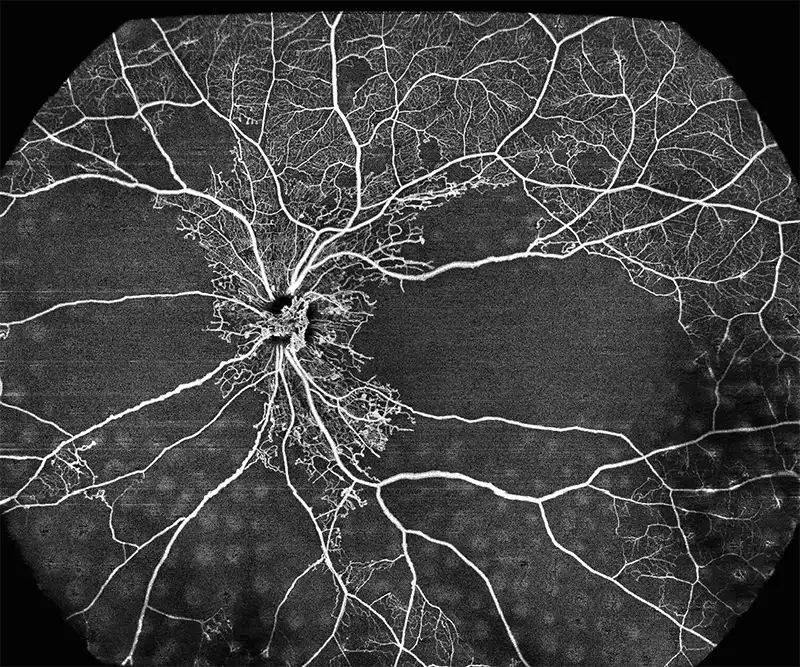

BMizar (BM-400K) es el OCT más potente de la industria con una fuente de barrido de 400 kHz. Su excepcional diseño óptico eleva la experiencia de la Angiografía OCT a un nivel sin precedentes. Con imágenes de alta definición de la retina, la coroides y el segmento anterior, cubre sin esfuerzo un área increíblemente grande en un solo escaneo (logrando un OCTA de 24 mm de ancho en solo 7-15 segundos).

Esta tecnología revolucionaria es un cambio de juego para las prácticas clínicas, particularmente en el diagnóstico y tratamiento de enfermedades como DR, RVO, RAO y más. Además, el BMizar ofrece un amplio rango de adaptación dióptrica, lo que hace factible realizar todo tipo de escaneos OCT/OCTA en pequeños animales como conejos, cobayas e incluso ratones sin necesidad de lentes adicionales. Es verdaderamente un equipo de ensueño para cualquier usuario de OCT.

Galería OCTs del TowardPi BMizar